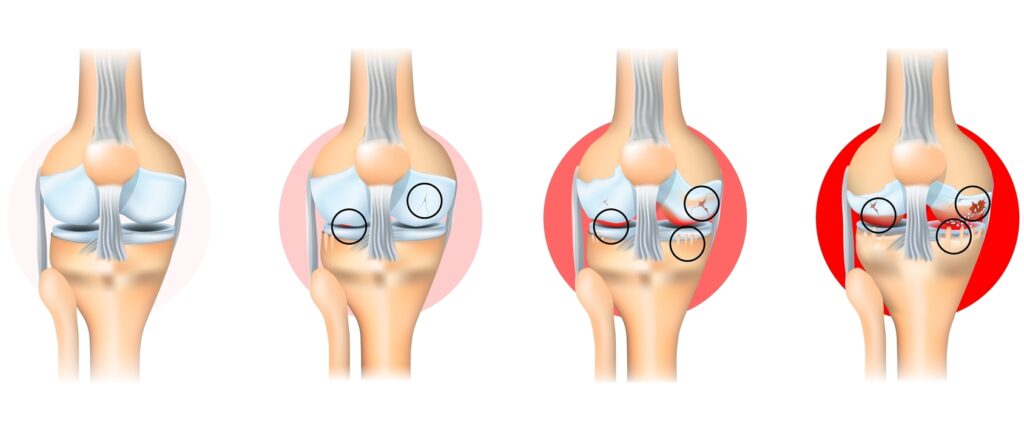

Condropatia (sau leziunea de cartilaj articular) reprezintă deteriorarea progresivă sau traumatică a cartilajului care acoperă suprafețele articulare ale genunchiului — în special rotula (patela), trohleea femurală și condilii femurali.

Atunci când acest strat se fisurează, se subțiază sau se desprinde, suprafețele osoase încep să se frece între ele, provocând durere, inflamație și uzură progresivă.

Condropatia poate fi localizată (o zonă mică de cartilaj afectat) sau difuză, implicând întreaga articulație — caz în care evoluează spre artroză.

- Scoruri de severitate: Outerbridge (gradele I–IV), care descrie profunzimea și extinderea leziunii.